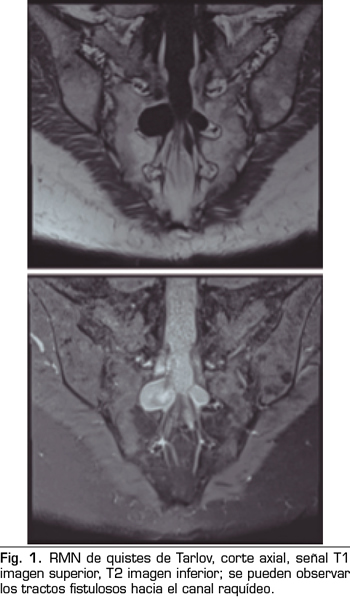

Los “quistes perineurales” o “Quistes de Tarlov” son alteraciones en la duramadre de las raíces nerviosas, que se producen más frecuentemente en la zona sacra. El diagnóstico suele ser casual mediante RMN; la incidencia es variable, debido a que el hallazgo es incidental. Habitualmente son asintomáticos, pero pueden producir radiculopatía, dolor perineal o vejiga neurógena, entre otros.

The diagnosis is usually casual by magnetic resonance. The incidence is variable, because the finding is incidental. The are usually asymptotic, but can cause radiculopathy, perineural pain or neurogenic bladder.